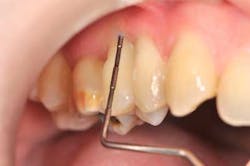

Tooth No. 4, because of its excessive bone loss, is further investigated. Probing is now normal (1.5 mm) — no bleeding, which indicates a gingival reattachment. This particular tooth mobility has improved from 4 to 2.

Fig. 4: Probing around tooth No. 4: 1.5 mm and no bleeding